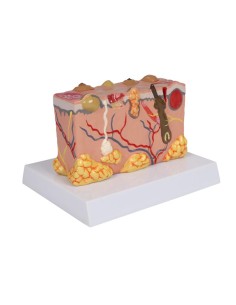

Scopri il Mondo dell’Anatomia con Modelli anatomici di Precisione

Benvenuto su Tuttoanatomia.it, il portale di riferimento in Italia per l’acquisto di modelli anatomici, poster, lettini portatili, simulatori medici e letteratura specialistica. Con i nostri modelli anatomici di 3B Scientific ed Erler Zimmer, leader mondiali nel settore, offriamo un’esperienza di apprendimento senza pari.

Modelli Anatomici Dettagliati per Ogni Necessità

Dal cranio in 22 parti con incastri magnetici ai modelli di colonna vertebrale, da quelli di articolazioni a quelli di cuore, ogni pezzo della nostra collezione è progettato per un’immersione totale nello studio dell’anatomia umana. I nostri modelli, realizzati tramite scansioni di ossa vere, garantiscono un’esperienza tattile autentica e una fedeltà di peso quasi identica agli originali.

Strumenti Didattici Innovativi per l’Educazione e la Pratica Medica

Essenziali per studenti e professionisti, i nostri modelli anatomici sono strumenti didattici che permettono di osservare le strutture anatomiche con precisione, eliminando la necessità di dissezioni o studi invasivi. Sono inoltre utili per spiegare ai pazienti le patologie, rendendo la comunicazione più efficace e risparmiando tempo prezioso.